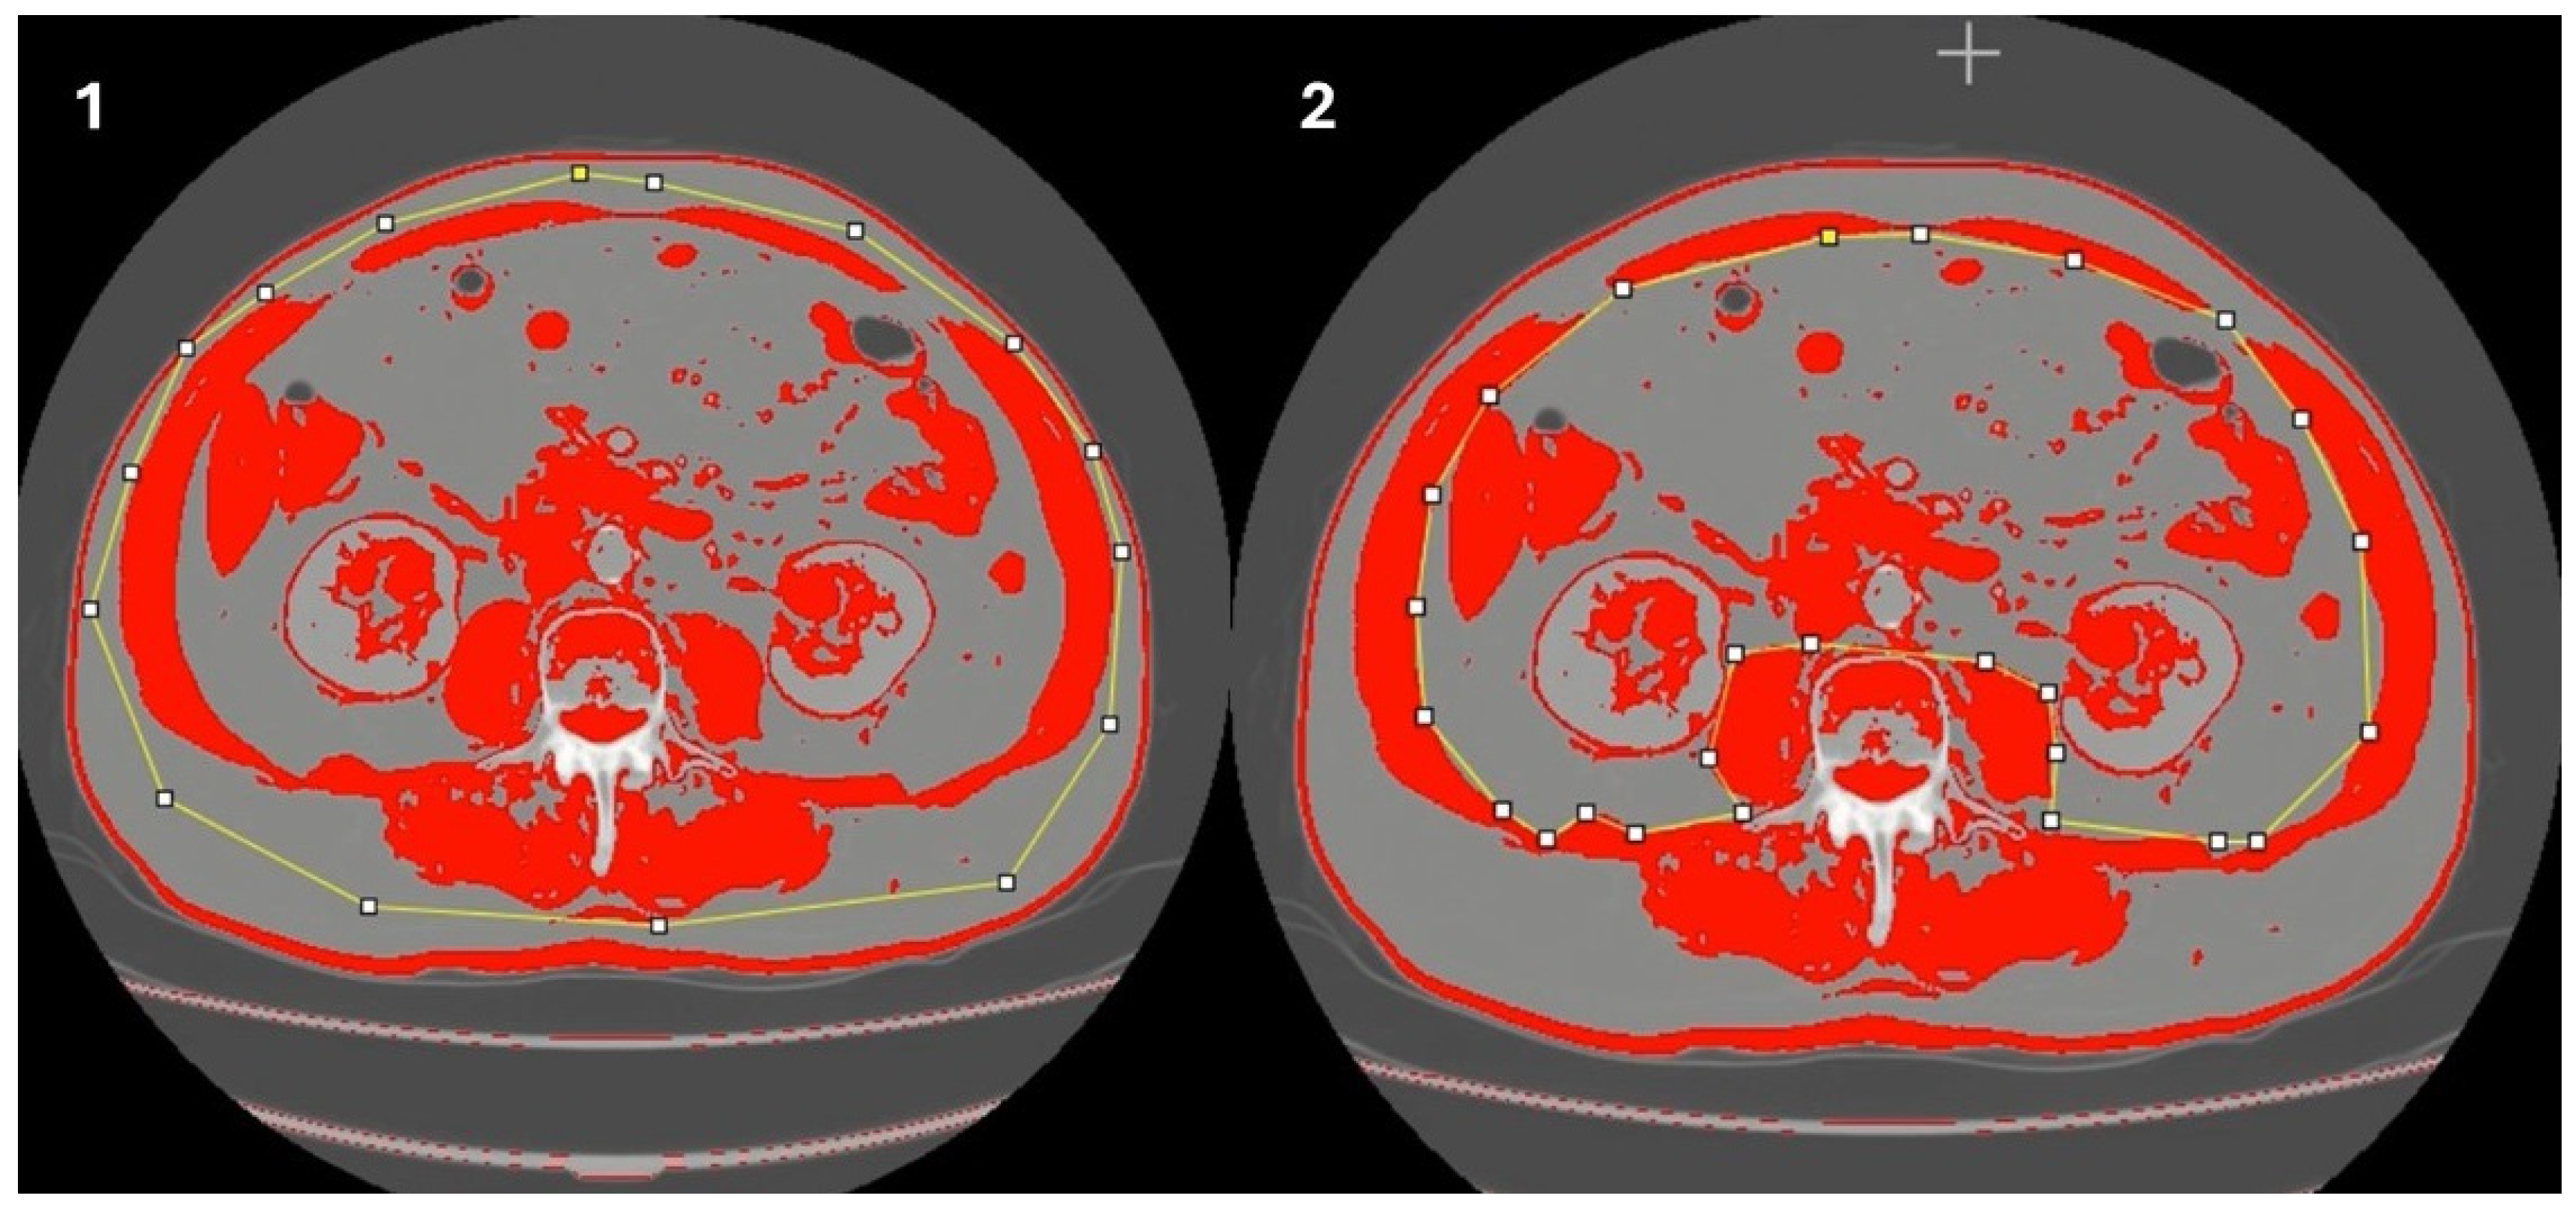

- Determination of muscle mass using computed tomography (CT scan)

- Gomez-Perez, S.L.; Haus, J.M.; Sheean, P.; Patel, B.; Mar, W.; Chaudhry, V.; McKeever, L.; Braunschweig, C. Measuring abdominal circumference and skeletal muscle from a single cross-sectional computed tomography image: A step-by-step guide for clinicians using National Institutes of Health ImageJ: A step-by-step guide for clinicians using national institutes of health ImageJ. JPEN J. Parenter. Enter. Nutr. 2016, 40, 308–318. [Google Scholar]